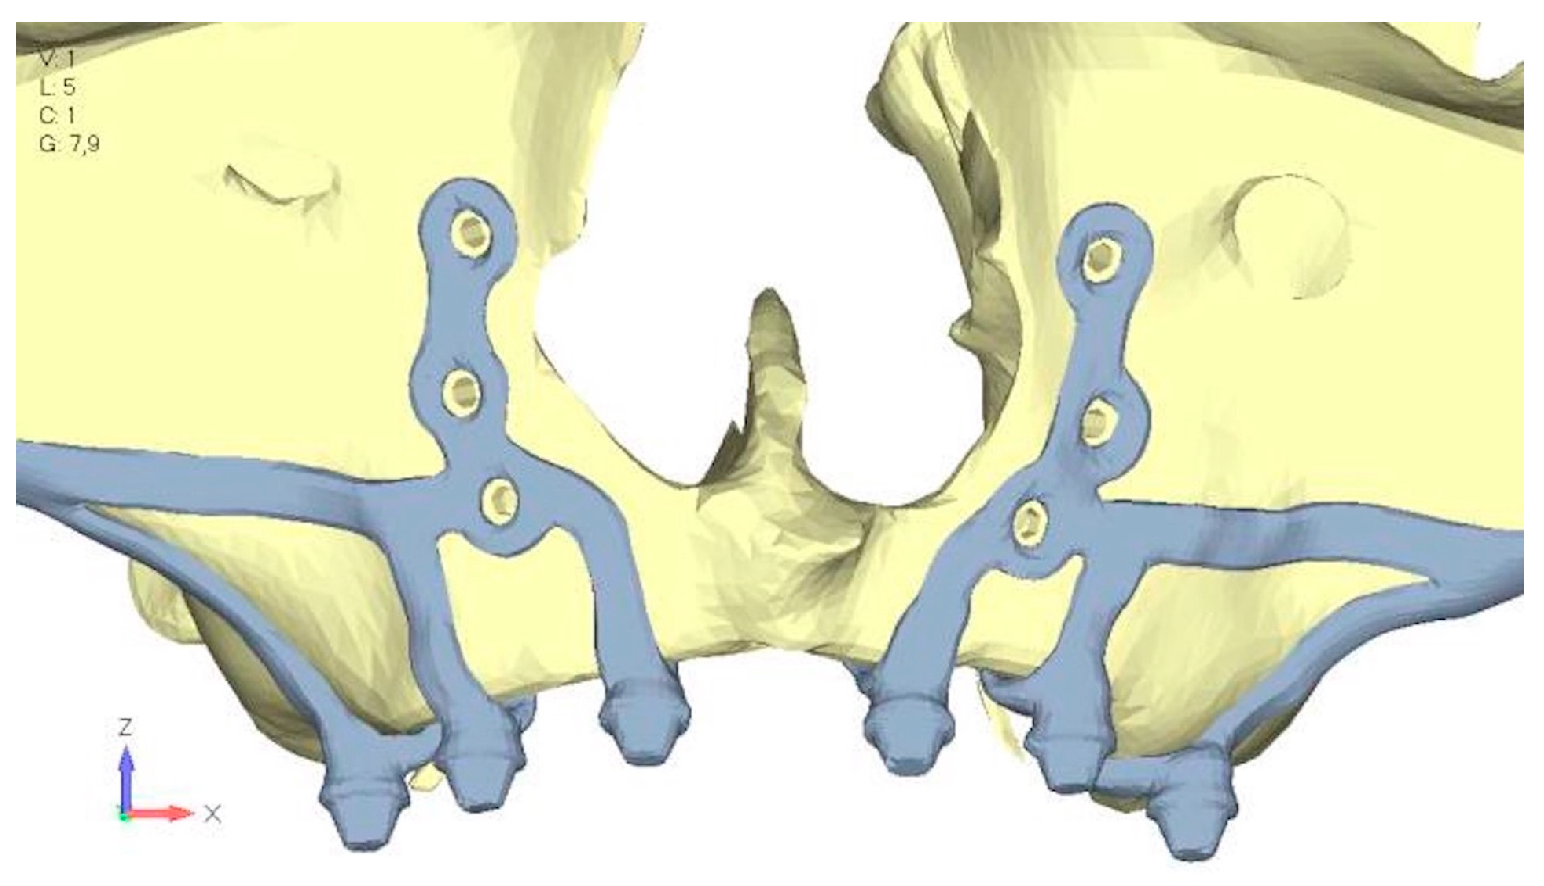

- Model V4. The previously added screw was relocated towards the frontal process, aligning it vertically with the other screws and ensuring that both arms of the first and second abutments connect to this screw (Figure 14). This solution proved to be more effective than V3; the addition of the screw reduces the stress on the other screws and on the support. The area where stress exceeds 50 MPa in the vicinity of the screws is now more contained, and the crestal support shows stresses between 30 and 35 MPa, which are absolutely acceptable (Figure 15a,b).